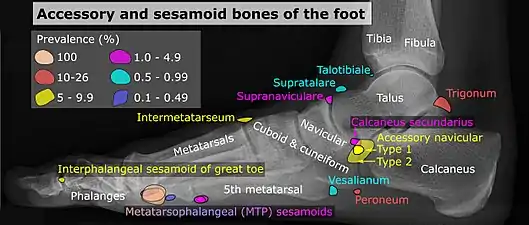

Lateral view.[11]

- 1 2 Reference list for image is located at Commons:Template:Accessory and sesamoid bones of the foot - references.